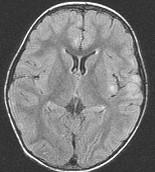

女,3岁,头痛、呕吐1周,请结合MRI图像,选择最可能的诊断是()A.脑膜炎B.硬膜下出血C.脑转移瘤D.脑梗死E.脑脓肿

问题 女,3岁,头痛、呕吐1周,请结合MRI图像,选择最可能的诊断是()

选项 A.脑膜炎 B.硬膜下出血 C.脑转移瘤 D.脑梗死 E.脑脓肿

答案 A